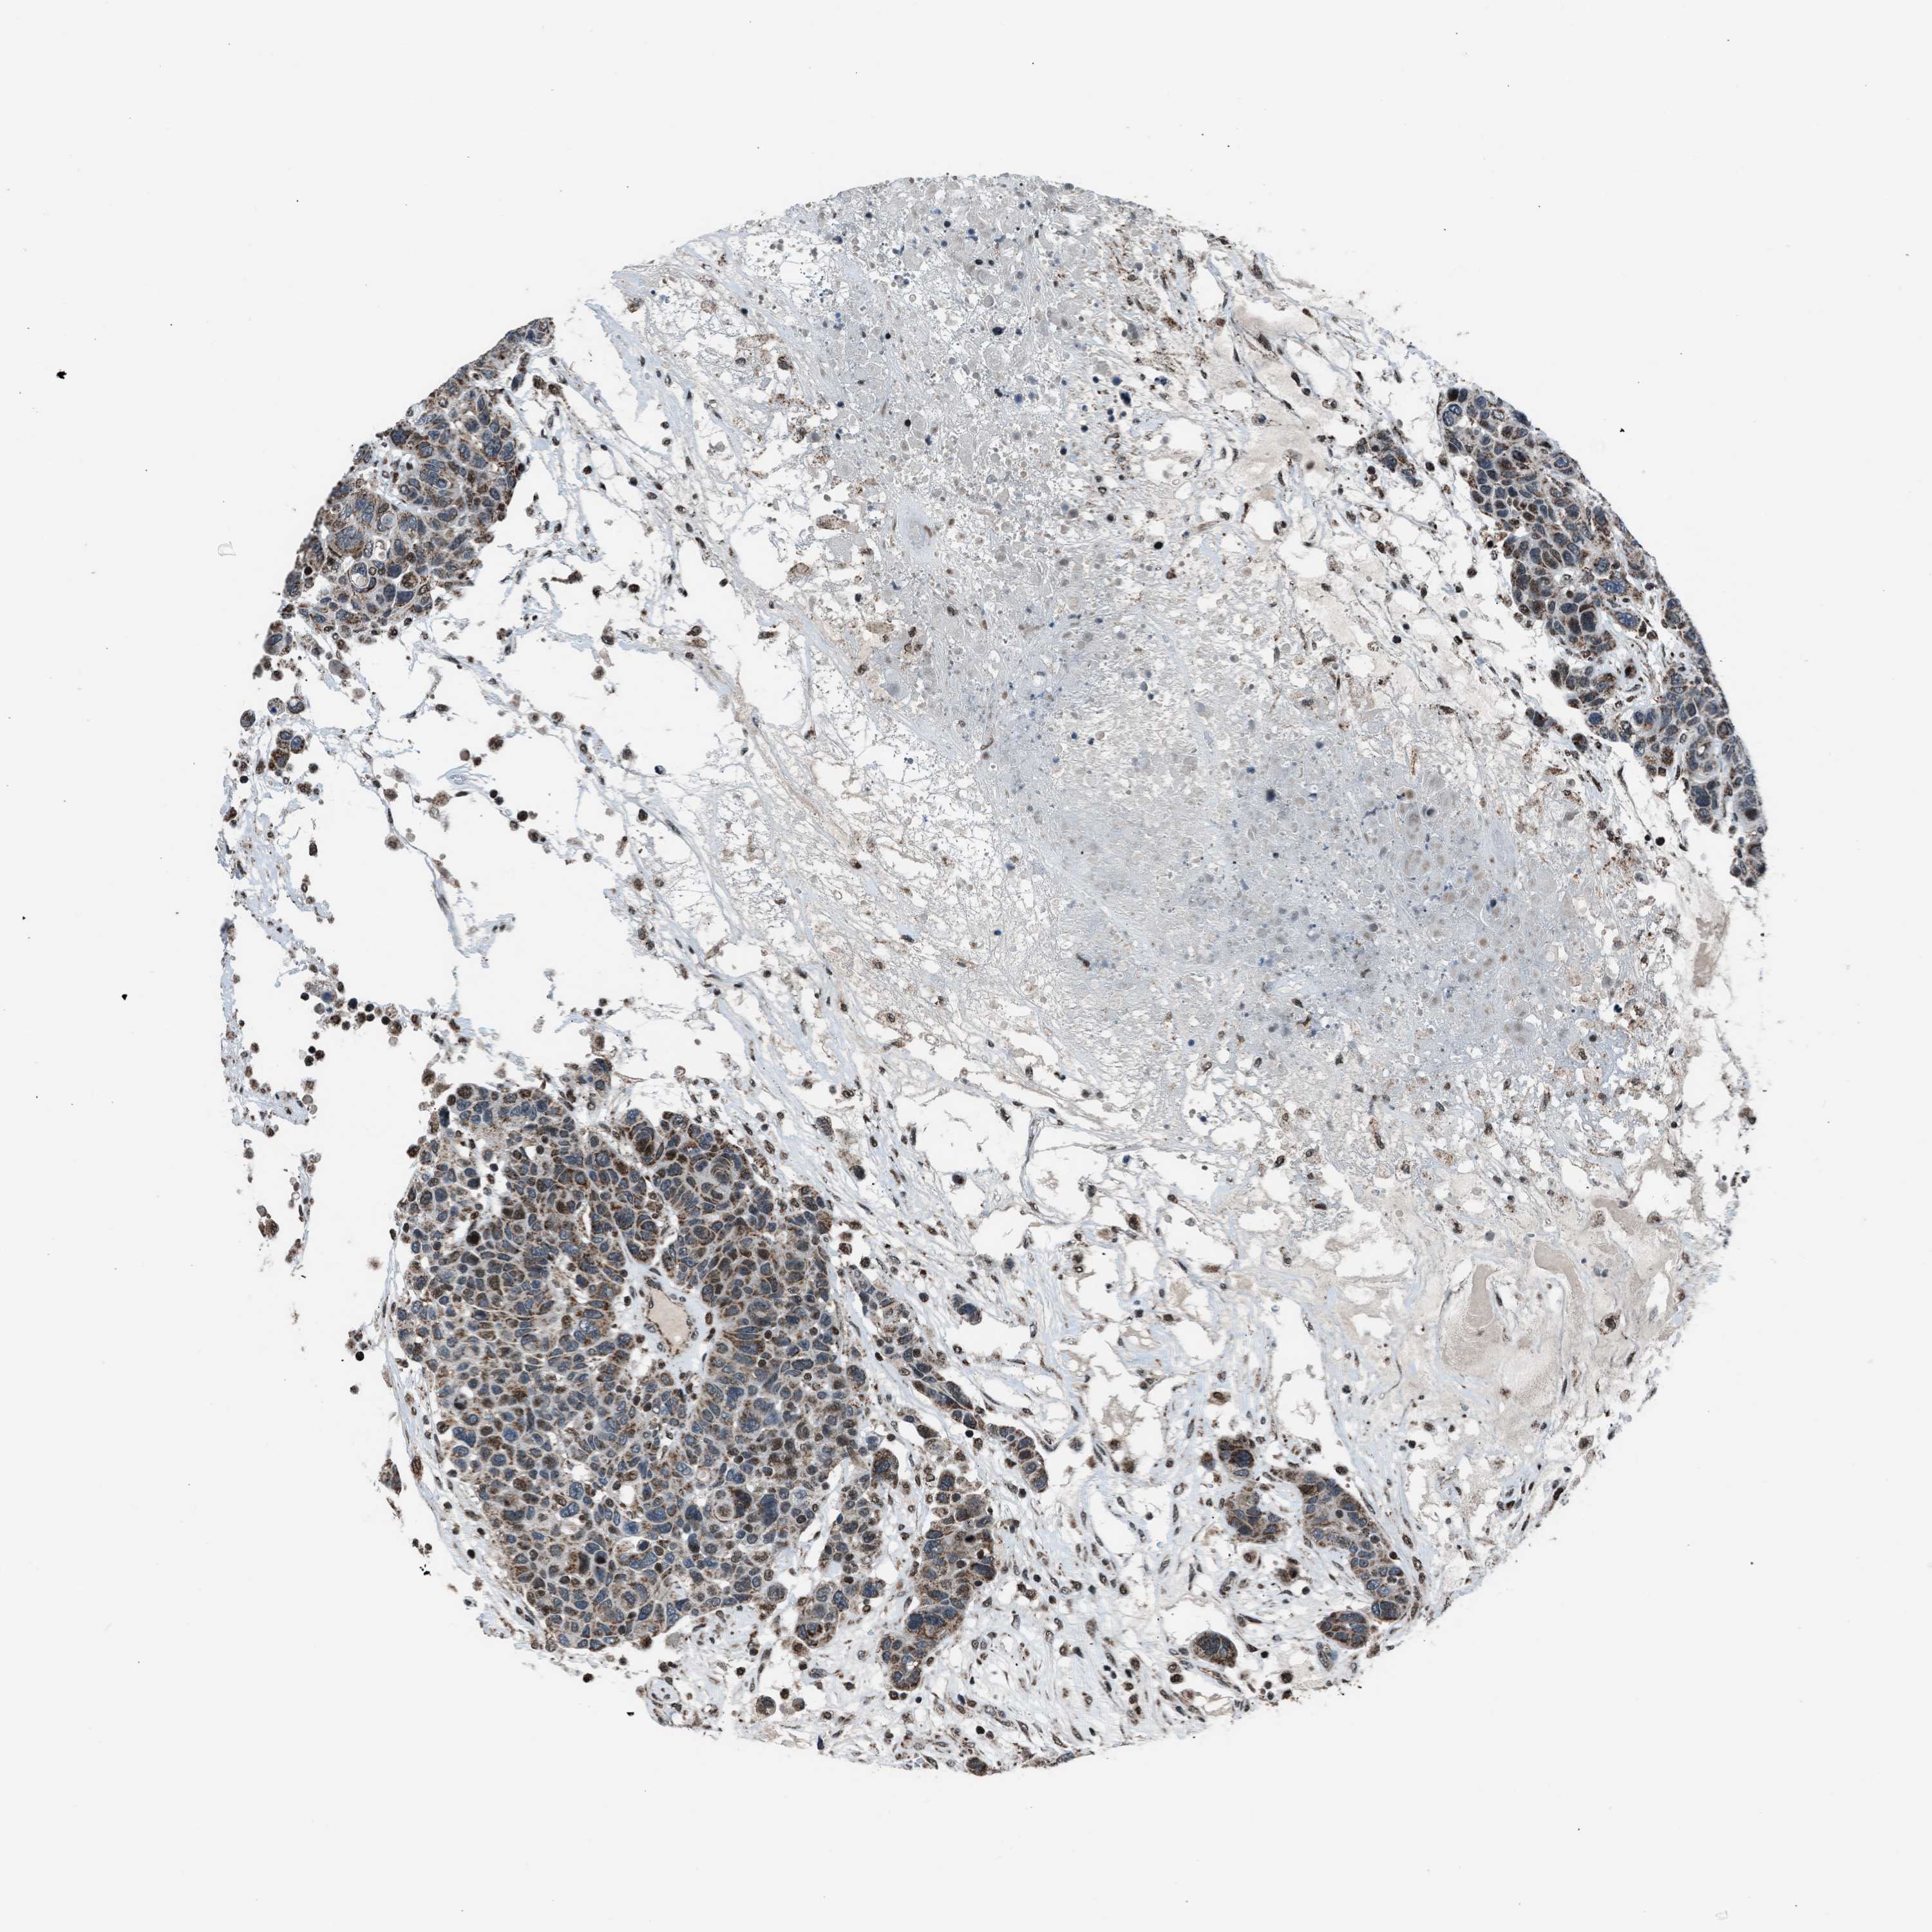

CANCER BREAST CANCER Show tissue menu

BRCA TCGA BRCA VALIDATION PROTEIN EXPRESSION